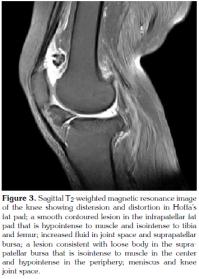

In the physical examination, the patient had an incision scar on the right knee. A difference of 5 cm was found in the right calf compared to the left calf. The right quadriceps muscle had an atrophic appearance. Palpation revealed no effusion. Active flexion of the right knee joint was limited to 110 degrees, and the end of the movement was painful. The right knee joint was capable of full active extension. Bilateral crepitations were present. Anteroposterior view of the X-ray scan showed joint space narrowing and coarse osteophytic formations predominately involving the medial compartment (Figure 1). A right lateral radiograph revealed opacity in the suprapatellar region and an ossific focus measuring 2.25 cm on the longitudinal axis and 2.75 cm on the horizontal axis, located in IFP (Figure 2). Magnetic resonance imaging (MRI) of the right knee showed increased fluid in the suprapatellar bursa and joint. There were loose body formations in the suprapatellar bursa and joint, and a smooth contoured lesion that was hypointense to muscle in the IFP (Figure 3). Routine biochemistry tests showed no abnormalities. The erythrocyte sedimentation rate was 43 mm/h, considered normal for the patient's age. Based on her medical history, physical examination and imaging findings, the patient was evaluated to have advanced Hoffa's disease developing secondary to past trauma or surgery, considering also the ossific focus later forming in the IFP region. Orthopedic consultation was requested. Surgery was recommended. However, medical treatment and physical therapy program was initiated for longterm monitoring, as since the patient did not have severe symptoms and did not consent to surgery. In the course of time, the patient's symptoms relieved.

In Hoffa's syndrome, there is increased T2 sequence signal due to edema and hemorrhage in MRI during the acute phase; and fibrin and hemosiderin build-up during the chronic phase. This is visualized as reduced T1 and T2 signals and a hypointense image on MRI. Magnetic resonance imaging also shows reduced signal activity in case of ossification. Therefore, X-ray findings are critical for the differential diagnosis. Intracapsular chondroma appears as a heterogeneous mass on MRI. Chondroid matrix and edema generate high signals, while signals are reduced with ossification.[10] The relationship between osteochondroma and Hoffa's syndrome is not yet clear. The most likely explanation is the following: IFP, which contains multipotent stromal cells, exercises which has a promoter effect due to impingement following recurrent traumas. This leads to differentiation into osteochondroma, which is however rare.[9]